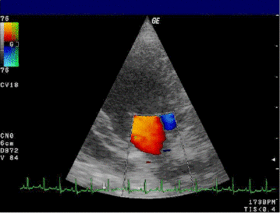

Doppler echocardiography is a procedure that uses ultrasound technology to examine the heart or blood vessels.[1] An echocardiogram uses high frequency sound waves to create an image of the heart while the use of Doppler technology allows determination of the speed and direction of blood flow by utilizing the Doppler effect.